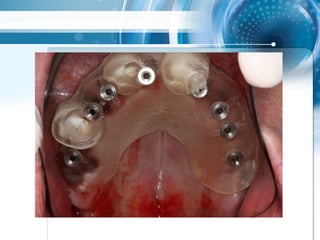

• zahngestützter surgical guide

Triple scan Technik

Triple scan Technik •zahngestützter surgical guide

• 48.